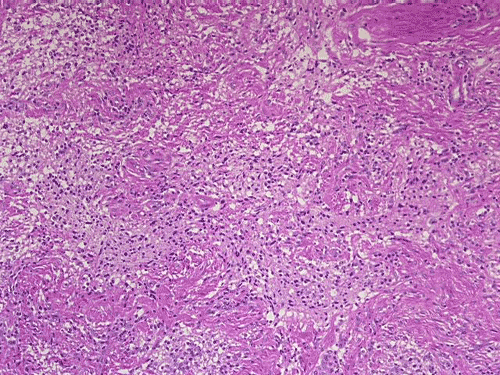

On low-magnification, cross section of the optic nerve gives a "double barrel" structure. The general outline of an optic nerve can still be appreciated (delimted by Þ in Panel A). There is a moderately cellular population of cells in between the dural sheath ( in Panel A) and the optic nerve. On medium-magnification, the vascular septa of the optic nerve is preserved (Panel B). On high-magnification, the optic nerve contains a mixture of cells with enlarged, mildly pleomorphic nuclei that are neoplastic astrocytes. Some cells with small nuclei are present and probably represent residual and reactive non-neoplastic astrocytes (Panel C and D). Cytoplasmic processes of some of tumor cells appear finely fibrillary (Panel C) while others are corase (Panel D). The cells in between the optic nerve and the dura is a mixture of irregular, hypercellular islands of neoplastic glial cells (delimted by Þ in Panel E) and hypocellular islands of slightly eosinophic, spindle cells. The later population represents reactive proliferation of meningothelial cells. The cytologic features are better appreciated in high-magnification (Panel F).

Microscopically, ONG in children are almost all pilocytic astrocytomas. The optic nerve is expanded. The fibrovascular septa within the optic nerve are separated by the tumor cells but the structure can still be well recognized as an optic nerve on cross section. Three major patterns are recognized 1. In the first pattern, the tumor is finely reticulated. In the second pattern, the tumor has microscysts and is coarsely reticulated. In the third pattern, the tumor cells are coarsely fibrillated, spindle shaped, and form bundles. There is minimal pleomorphism in the nuclei and it is not always easy to separate the neoplastic cells from adjacent reactive gliosis. There is a usually lack in mitotic activity, endothelial proliferation, and necrosis. Immunohistochemistry, the tumor cells are strongly reactive for glial fibrillary acidic protein (GFAP).

ONGs often extend into the subarachnoid space and inflict a prominent proliferation and thickening of perioptic meninges. This proliferation is composed of meningothelial cells, fibroblasts, and neoplastic astrocytes. Such changes are also known as arachnoidal hyperplasia or arachnoidal gliomatosis. The tumor tends to have coarsely fibrillated spindle cells may not be easily to be separated from the meningothelial cells and fibroblasts due to the intermingled architecture. Immunohistochemistry for GFAP is very helpful in separating the two components.